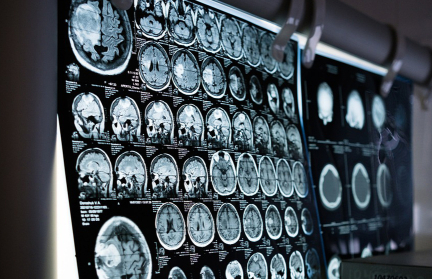

Neuralink ищет нового добровольца для имплантации после неудачи с первым

Предыдущий эксперимент Neuralink по подключению мозга к компьютеру прошел не совсем удачно, сообщает Forbes.

Согласно имеющейся информации, у первого добровольца, которому вживили в мозг чип, отошли провода. Это привело к ухудшению качества передачи сигнала.

Отмечается, что подобные проблемы имелись еще на стадии испытаний на животных. Сейчас же планируется испробовать эту технологию на человеке еще раз.

Создание подобного нейроинтерфейса может иметь массу применений – от управления компьютера «силой мысли» до использования киберпротезов, которые почти способны работать как обычные конечности.